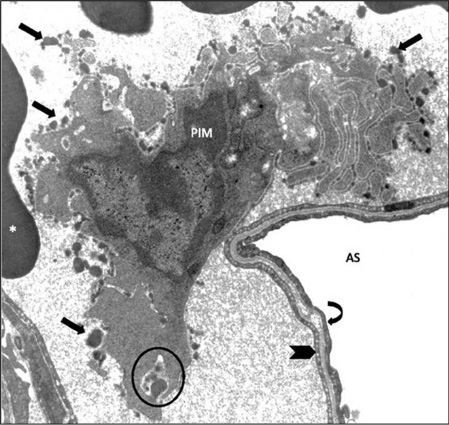

PIMs have a significant ability for adherence, which is one of the most important characteristics of these cells. They firmly attach to the capillary endothelium via junction-like intercellular adhesion plaques (ICAPs), as demonstrated for the case of a sheep PIM cells adhered to the pulmonary capillary endothelium (Figure 2). In addition to pulmonary capillaries, in vitro PIM cells adhere via adhesion plaques to pulmonary artery and corneal and aorta segments (21). The intercellular space between the PIM cell membrane and adherence surface is 15–20 nm and electron dense material is present on both sides of the cell membranes with a width of about 30 nm (26).

Figure 2: Pulmonary Intravascular Macrophage (PIM) of a sheep, anchored to the pulmonary capillary endothelium.Unique ruffled globular membrane structure (arrows) is present. AS, alveolar space; *, red blood cells; circle, phagocytosis; thick arrow, capillary wall; curved arrow, aveolar epithelium; magnification, X10,000. Modified from Ref. (25).

Figure 2:

Pulmonary Intravascular Macrophage (PIM) of a sheep, anchored to the pulmonary capillary endothelium.

Unique ruffled globular membrane structure (arrows) is present. AS, alveolar space; *, red blood cells; circle, phagocytosis; thick arrow, capillary wall; curved arrow, aveolar epithelium; magnification, X10,000. Modified from Ref. (25).